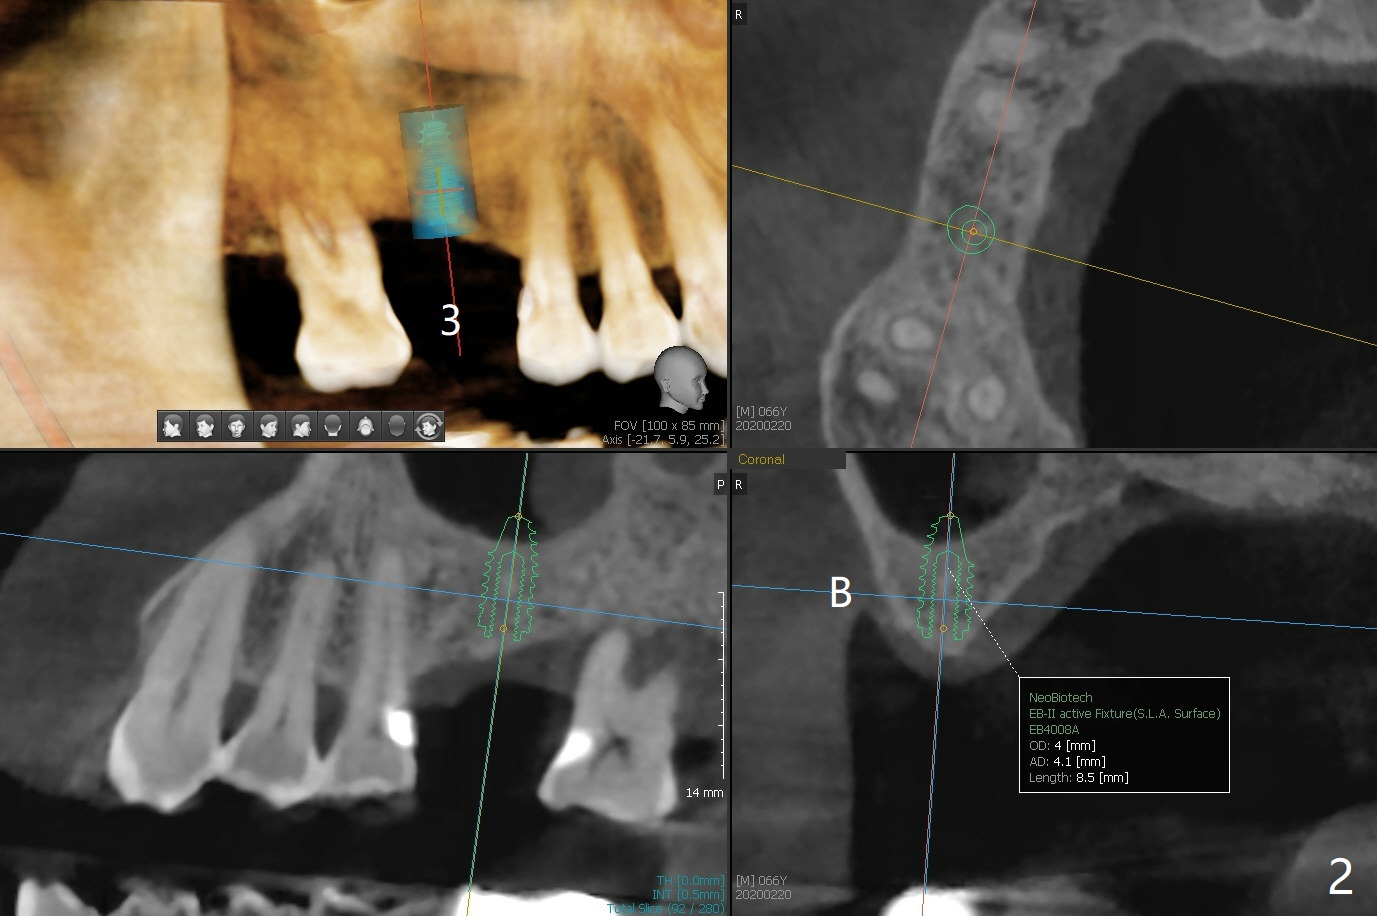

A 66-year-old man returns for #3 implant 1 month post #14 cementa-tion (Fig.1). The latter was placed free hand because of emergency (tooth fracture). The distal threads are exposed (<) probably related to shallow placement (imprecision) or insufficient bone graft. In spite of the wide ridge at #31 (data not shown), there is bone loss around the extremely large implant (<). In contrast, the ridge at #3 is narrow (Fig.2). A small implant (4x11 mm tissue-level) will be placed precisely in depth and position relative to the ridge with guide.